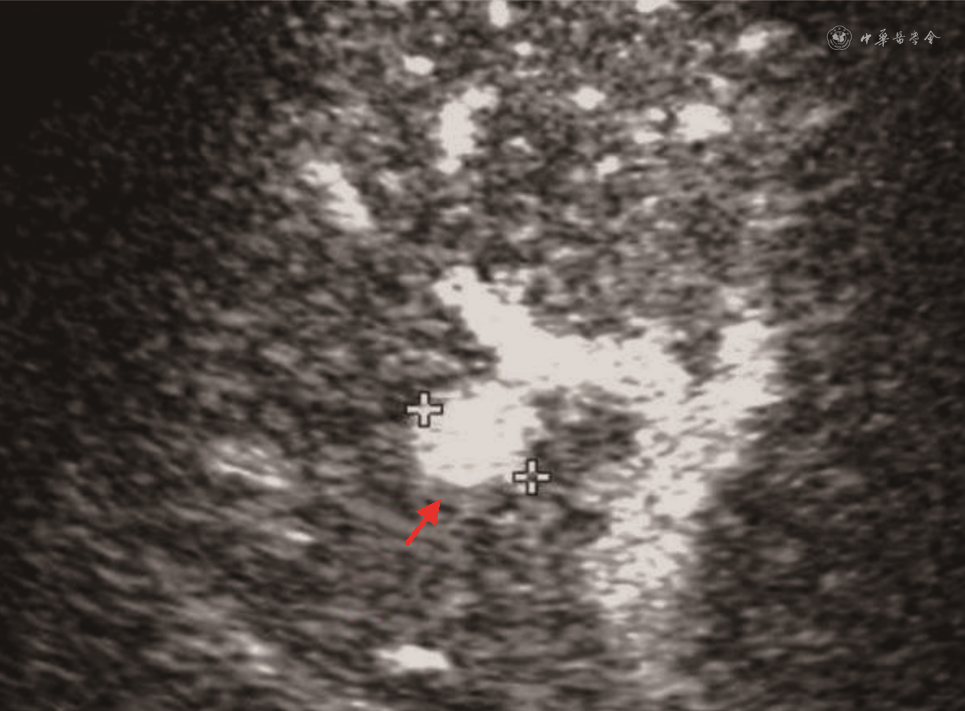

(1)HAT:HAT发生率为4%~12%,是肝移植术后最常见的肝动脉并发症,占移植后血管并发症60%。HAT的中位发生时间是移植后6.9 d[49, 50],约70%发生在吻合口。CDFI是目前筛查HAT的首选方法,在肝门、肝内外均未测及肝动脉血流,高度提示HAT[51]。CDFI诊断HAT的准确度60%~92%,移植后早期肝脏肿胀、肝动脉内径细小(1~3 mm)及术后血管痉挛均可使肝动脉显示困难,导致假阳性;而出现肝动脉—门静脉瘘或肝动脉血栓闭塞伴肝动脉侧支形成(最早于术后2周形成)时,又常因为CDFI检测到肝内动脉血流,导致假阴性发生[52, 53]。CDFI疑诊HAT时,应立即进行床旁超声造影或CTA及DSA检查。超声造影时如在门静脉显影前始终不能见到肝动脉显影可诊断HAT,有很高的阳性预测值(92.9%)及阴性预测值(100%)[54]。CDFI检测不到肝动脉血流疑诊HAT时,应用超声造影可以减少60%以上的不必要DSA检查[55, 56](图11)。同时,超声造影可明显缩短肝动脉超声检查所需时间,检查时不受患者心脏搏动、呼吸运动等造成的多普勒伪像干扰[57]。HAT可导致移植肝胆管壁缺血坏死及移植肝实质梗死。移植肝梗死灶声像图表现为近肝包膜处楔形不均匀低回声区,超声造影或增强CT表现为低灌注或无灌注区。